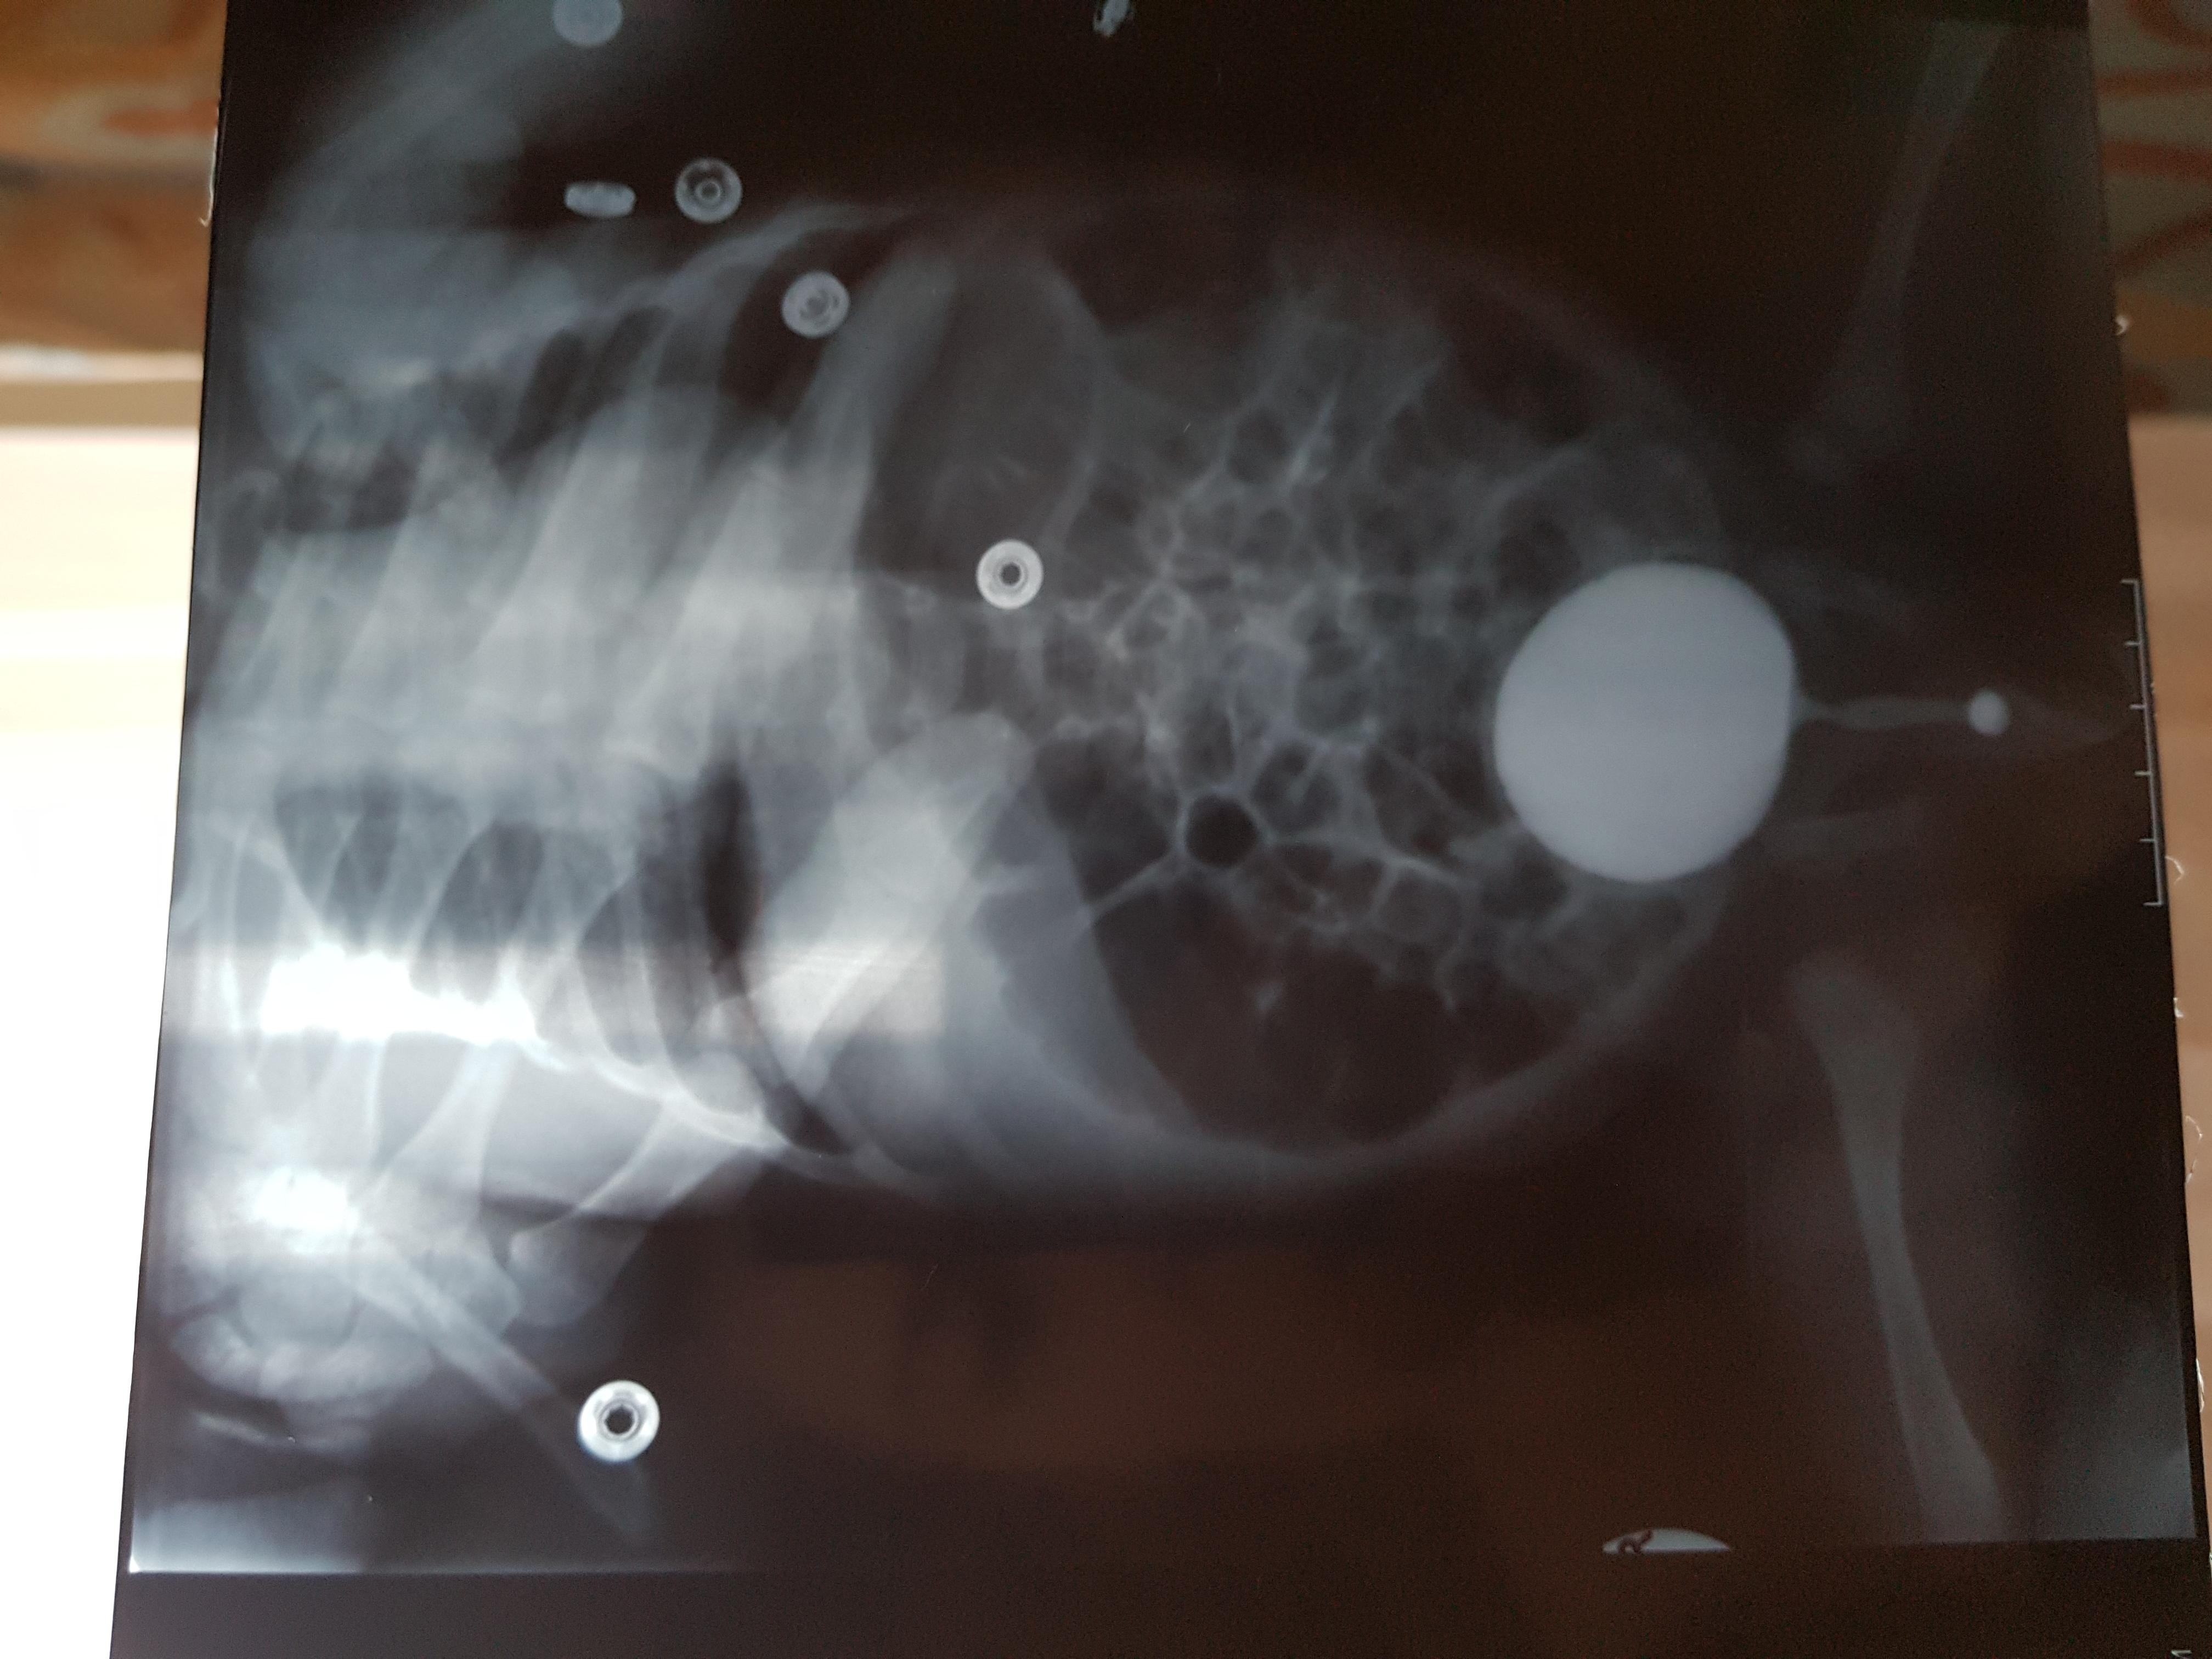

Добрый день! Еще внутриутробно у ребенка обнаружили расширение лоханок.Провели обследование в 1.5 месяца.Поставили диагноз болезнь Ормонда.И назначили консервативное лечение.В 2ух мочеточниках по несколько наростов.рефлюкса не было.Скажиье, возмлжнл что ребенок поосто перерастет?

Болезнь Ормонда (ретроперитонеальный фиброз, забрюшинный фиброз) – хроническое воспаление жировой клетчатки забрюшинного пространства, которое постепенно приводит к компрессии и нарушению проходимости трубчатых структур данного анатомического участка. Чаще всего, в качестве этих тубулярных структур выступают мочеточники.

У меня есть сомнения, что причиной гидронефроза в Вашем случае явилось именно это состояние.

Возможно речь идет о пузырно-мочеточниковом рефлюксе.